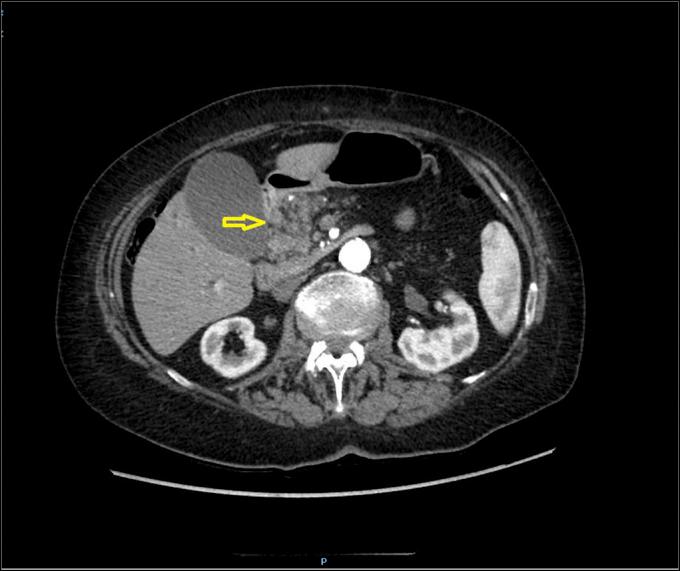

The palliation of simultaneous biliary and duodenal obstruction in patients with advanced pancreatic cancer is a clinically and technically challenging scenario. Endoscopic procedures are a valid alternative to surgical or percutaneous transhepatic biliary drainage. The availability of self-expanding metal stents (SEMSs) and lumen-apposing metal stents (LAMS) have expanded therapeutic options. We describe a case in which biliary and duodenal obstructions were treated successfully with the combined use of SEMS and LAMS devices. Endoscopic ultrasound-guided biliary drainage with the use of new LAMS and a duodenal SEMS can be a valid option in expert hands as a palliative and minimally invasive treatment for gastric outlet and biliary obstruction.

晚期胰腺癌患者同时出现胆管和十二指肠梗阻的姑息治疗在临床和技术上是一个具有挑战性的情况。内镜手术是手术或经皮经肝胆道引流的有效替代方法。自膨式金属支架(SEMS)和管腔贴附金属支架(LAMS)的应用扩大了治疗选择。我们描述了一例通过联合使用SEMS和LAMS设备成功治疗胆管和十二指肠梗阻的病例。在内镜超声引导下使用新型LAMS和十二指肠SEMS进行胆道引流,对于有经验的医生来说,可作为胃出口和胆管梗阻的一种有效的姑息性微创治疗选择。